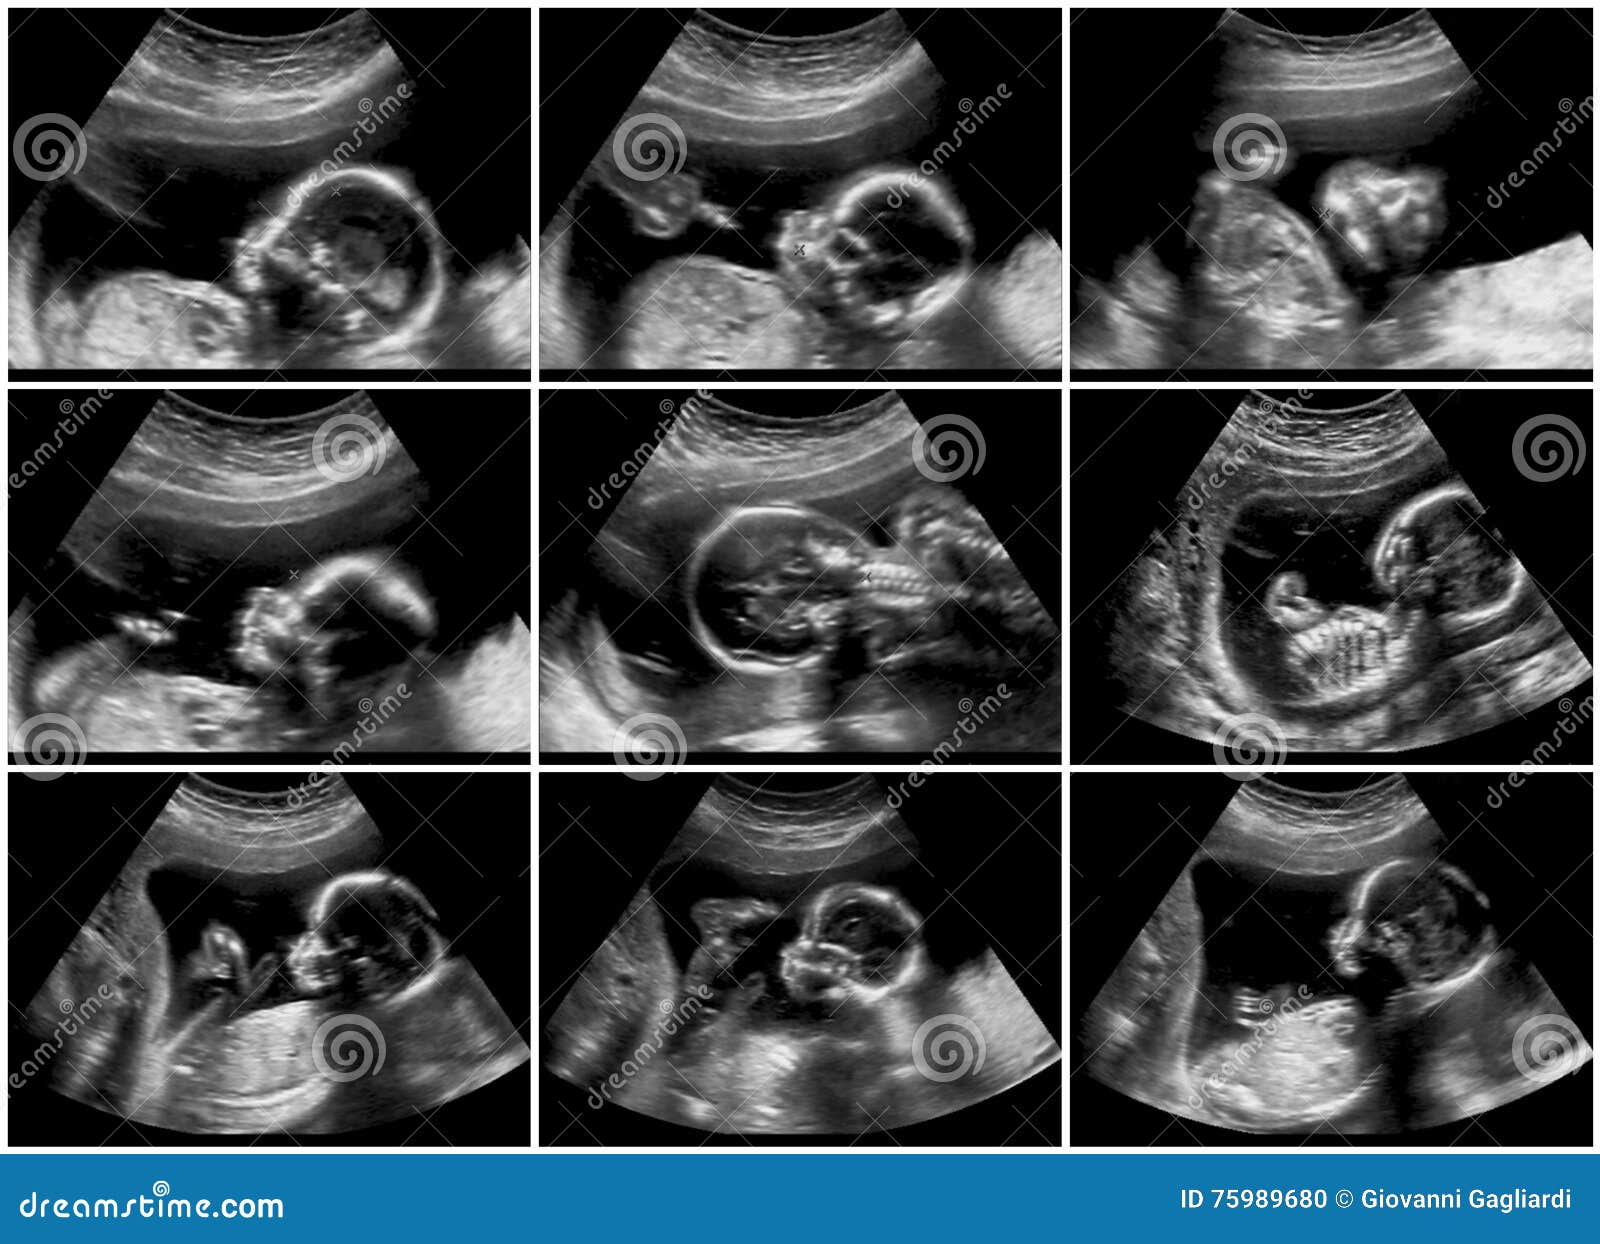

Как выглядит ребенок на узи фото в 10 недель?

На этой стадии беременности ребенок становится все более осознанным и активным. Узи фотографии показывают, что его плодовой мешок становится уже образованным, а сердцебиение можно услышать с помощью узи аппарата.

Хотя пока еще рано говорить о половой принадлежности ребенка на узи фото, уже можно увидеть формирование его черт лица. Глаза, нос, губы - все более четко проглядывается на узи снимках.